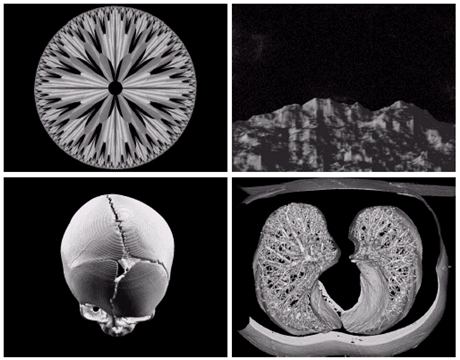

Other imaging modalities

- 지진 모델의 단면영상(화살표는 석유와 가스 트랲을 가리킴)

a)아기1 b)아기2 c)갑상선 d)손상된근육

- 전자현미경: SEM(scanning electron microscope)

- 전자빔을 쏘아 각 위치에서 빔과 샘플과의 상호작용을 기록

텅스텐필라멘트의 250x SEM영상, 손상된 IC의 250x SEM영상